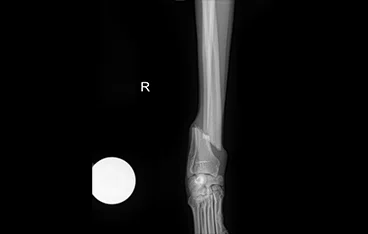

• 각기형(ALD)

• 각기형(ALD) 수술 전

각기형(ALD) 수술 후